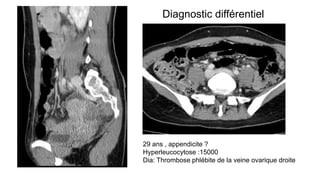

29 ans , appendicite ?

Hyperleucocytose :15000

Dia: Thrombose phlébite de la veine ovarique droite

Diagnostic différentiel